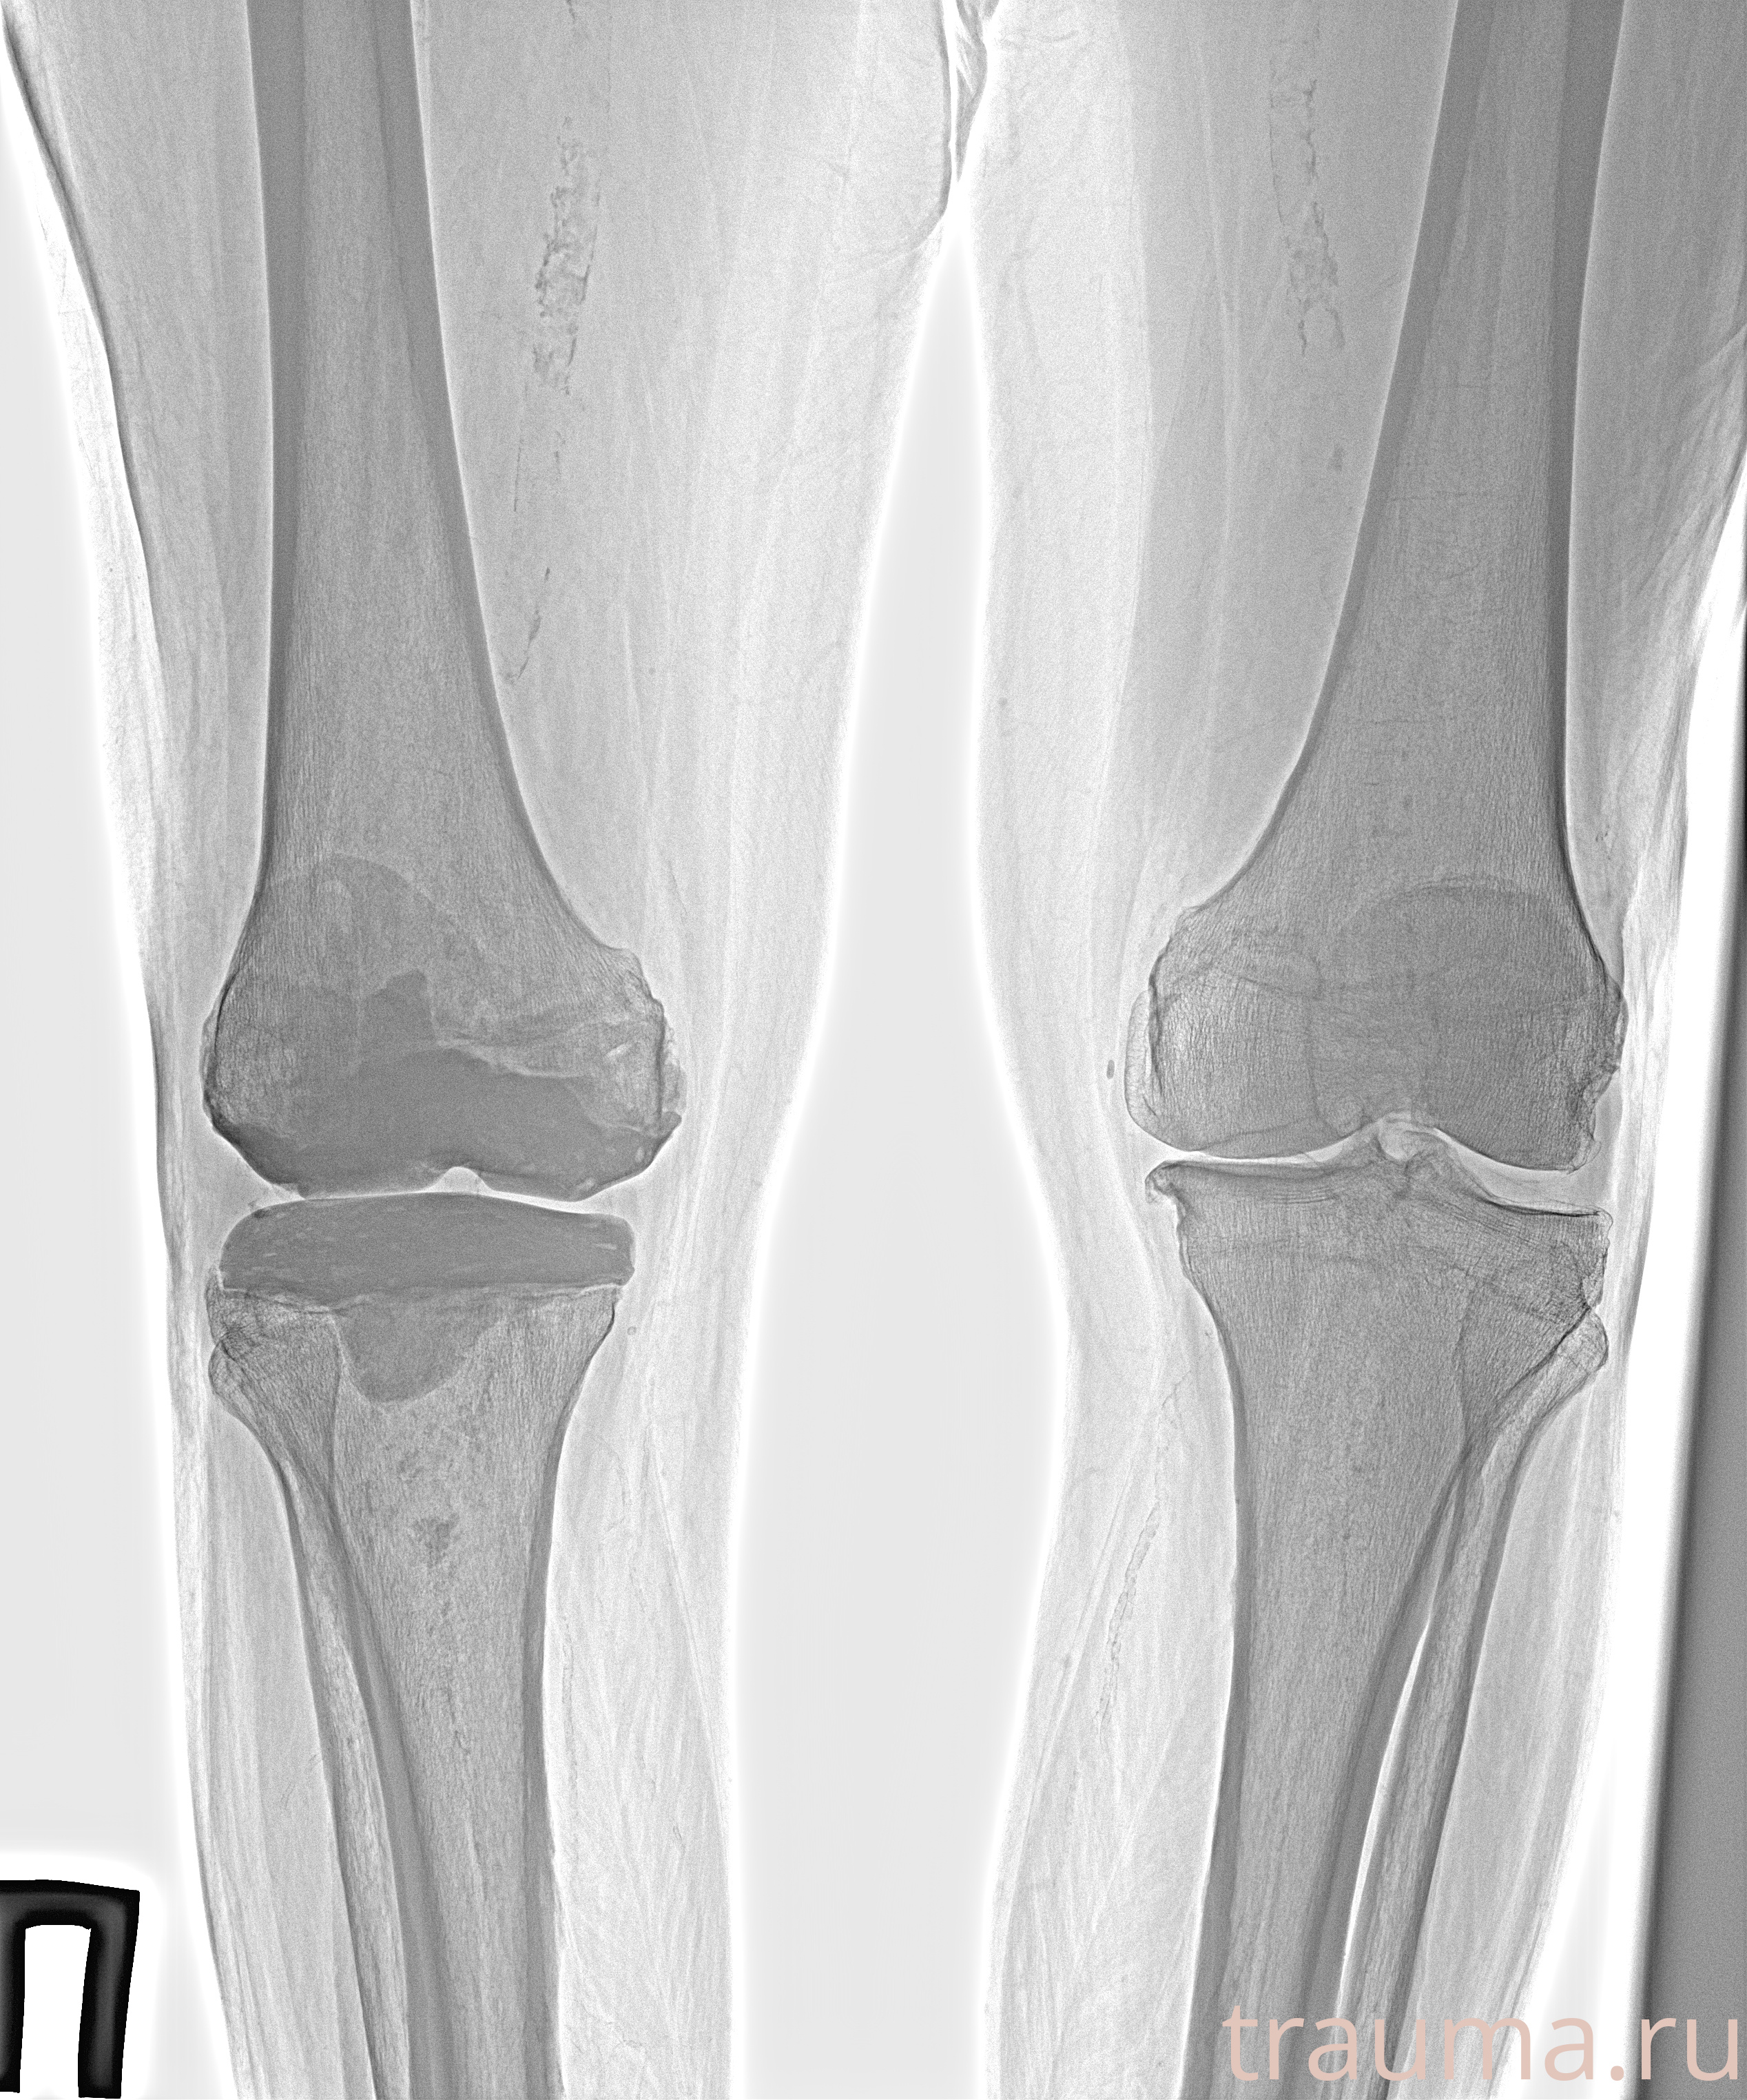

Рентгенограммы

Рентген на дому: по вашему адресу приезжает врач-рентгенолог, травматолог-ортопед с мобильным рентгеновским аппаратом, проводит диагностику травмы или заболевания, делает необходимые рентгенограммы, дает рекомендации по дальнейшему лечению. Получить качественные снимки в домашних условиях возможно благодаря уникальной методике, разработанной МосРентген Центром для института  Склифосовского